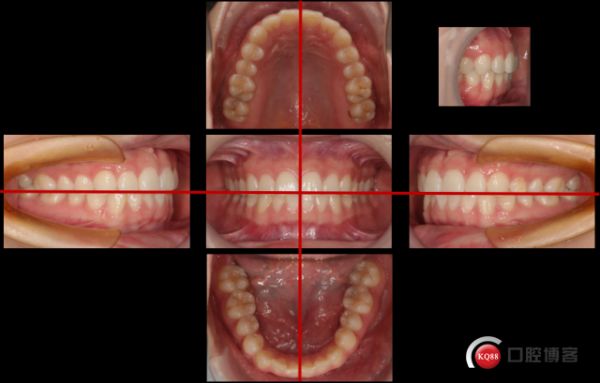

口內(nèi)照片是對牙齒組織和軟組織的整體印象,各牙齒的位置、角度及長度之間的關系都能夠看到,可以全面展現(xiàn)出牙齦曲線,軟組織健康程度和存在的美學問題。 一般需要拍攝6張:牙尖交錯位時的正面、左右側及上下牙弓合面以及覆合覆蓋的特寫。

拍攝全牙弓咬合影像時,一般要求患者端坐或呈45°體位躺于牙科椅上,由助手進行雙側牽拉,拍攝者上身前傾,左腳向前邁出,兩腳打開適當距離,穩(wěn)定身體。拍攝者上身前傾,左腳向前邁出,兩腳打開適當距離,穩(wěn)定身體。拍攝時,囑患者牙齒咬于正中,將口角拉鉤放于口腔前庭,再向兩側、向前拉緊,避免接觸到牙齒,暴露全部牙齒、唇側牙齦、粘膜、系帶和咬合關系。拉鉤手柄中央與咬合平面位于一條直線,拍攝者位于患者正前方,鏡頭平面與畫面上下緣平面平行且等距離,牙弓中線(如果正常)與畫面垂線中線一致。焦點于中切牙,構圖以上中切牙為中心,包含全牙列的牙齒、軟組織,盡量少暴露牽拉器,并將嘴唇排除在外。影像的水平中線是上頜前牙的切端連線,垂直中線是面部中線,左右頰間隙均等,從正中到左右的牙齒數(shù)量相等,咬合平面與鏡頭線呈水平(橫向),咬合平面均分構圖。

覆合覆蓋影像,拍攝時體位與正位咬合像相同,拍攝側拉鉤適當向后牽拉,至少暴露完整的尖牙,拍攝者轉移至患者右側,平行于咬合平面拍攝,對焦中心位于尖牙。

頰側咬合影像:完整的頰側咬合像以第一前磨牙為中線,包括整個牙列,可以清楚的看到后牙形態(tài)、排列及合關系;對于牙列缺損患者,還可以觀察對頜牙的伸長、鄰牙的傾斜問題,評價骨吸收等情況。

拍攝時,拍攝者左手持側方口角拉鉤,向遠中、外牽拉,避免接觸到牙齒,暴露被攝側牙齒、牙齦、粘膜、系帶和咬合關系,右手持相機位于患者側前方,與患者成45°,助手持正位拉鉤輕輕牽拉對側口角,保證拍攝視野清晰。聚焦位置為第一前磨牙區(qū),拍攝包括整個牙列直至最后的磨牙,口角拉鉤中央與咬合平面位于一條直線,咬合平面與畫面上下緣平行且等距離。

上下頜牙弓合面影像中可以反映牙弓形態(tài)、牙齒排列、切端位置等美學信息,是進行美學牙科相關治療前測量、計算、美學設計的重要影像,也是綜合治療前反映已經(jīng)存在的充填體、磨耗情況等問題的重要影像。

拍攝上頜牙弓頜面像時,應調整椅位至患者幾乎呈仰臥位,拍攝者站在患者頭部,從上面拍照。助手站在患者左側,右手拿壓唇板牽開口周唇組織,左手拿三用槍將反光板輕輕吹干以保持視野清潔干燥。拍攝下頜時,拍攝者位于患者右側,助手左手拿壓唇板牽拉唇組織,右手拿三用槍吹干反光板。囑患者張大口,需注意反光板后端不要過于接近拍攝側牙齒,以避免形成雙重影像。拍攝時對焦中心在前磨牙咬合區(qū)連線的中點處,助手將患者的唇、頰組織向外充分牽拉,盡量使包括第二磨牙遠中的整個牙弓全部暴露出來,反光板的邊緣和嘴唇要盡量少進入構圖以內(nèi)。